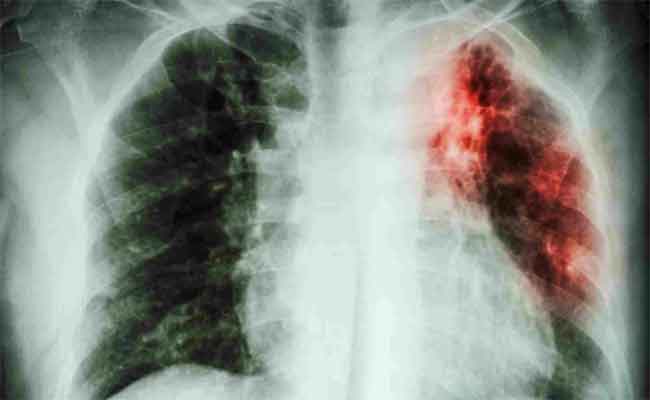

يُعتبر التليف الرئوي من أمراض الرئة الأشدّ خطورة. وكلمة تليّف يُقصد بها السماكة، اذ أنّ الجدران اللاصقة الرقيقة عادة للأكياس الهوائية في الرئتين تصبح سميكة وصلبة ما يؤدي الى بنية رئة أكثر صل... اقرأ المزيد